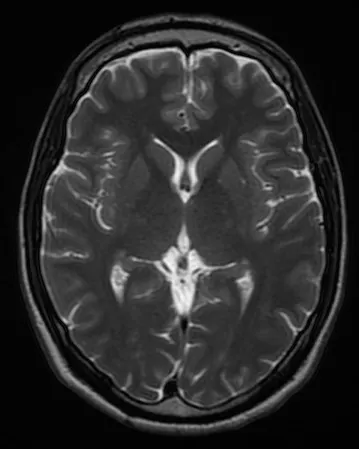

MRI of the brain:

Reminds me that all of the thoughts that I have ever thought have taken place in this relatively small space in side my head.

Makes you wonder how the brain is constructed such that we’re able to be conscious and aware. Does the structure of the brain give it it’s function? or is there something external that we’ll never know that makes us conscious?

It also makes you think about what would happen if brains could be as large as needed without being constrained by the volume of the cranium. Our brains can’t grow any larger than our skull permits. Computers are not constrained by very much, other than the surface are of the earth and atmosphere height. How much more powerful would a computer’s mind be than ours if it was just 4x the size by volume as ours? Makes you think.

Going off of the point above, it makes you think that if a creature had it’s brain that was like 2x the size of our brain, (and probably consumed like 4x the power), then it probably wouldn’t be evolutionarily viable, because the energy consumption required wouldn’t be worth it, especially in the early stages of life when all that’s available is essentially trees, rocks and dirt. Maybe humans are at that point where we’re able to consume just enough energy early on by our minds to make it out of the stone ages, but just smart enough to be able to make minds that are smarter than ours.